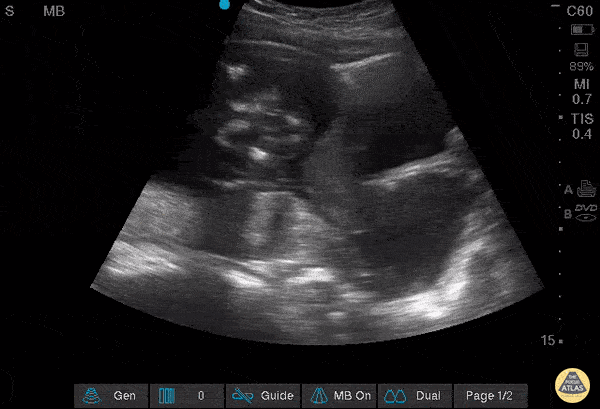

OB/Gyn - Dilated Cervix with intact membranes protruding out

17 YOF, G1P0 and 18 weeks pregnant, who presents to the ER with the complaint of "feeling like something was coming out" of her vagina since this morning. Mild lower back pain. Denies pelvic pain, vaginal bleeding, or leaking fluid. US shows dilated cervix with intact membranes protruding out. Vicky Lam @vickylalaloo